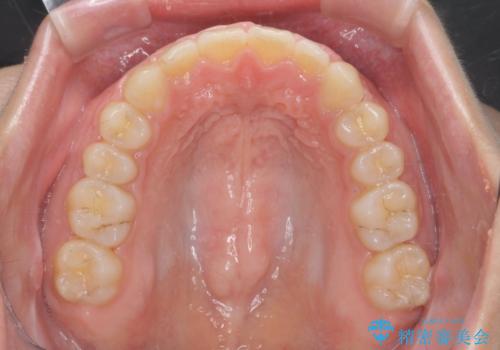

深い噛み合わせ、すきっ歯の改善 ワイヤーを用いたマルチブラケット矯正

ワイヤーを用いたマルチブラケット矯正を行うことで深い噛み合わせを改善し、前歯の隙間もなくし審美的な歯列へと治療をおこなっていきます。

深い噛み合わせの改善は前歯の圧下が必要なため、治療期間が長期化することが多いです。